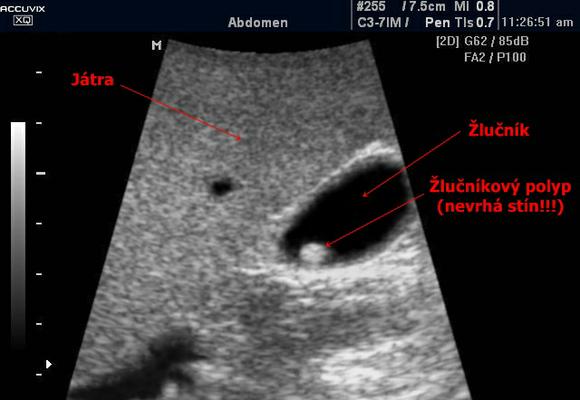

Для обнаружения полипа используют способ УЗИ. С помощью данного метода возможно обнаружить примерно девяноста процентов выростов. Но наиболее точные сведения можно добыть при эндоскопическом ультрасонографии. Гибкий эндоскоп, к которому прикреплен датчик, дает возможность получения послойной картинки стенок ЖП и выявить наличие патологических разрастаний незначительных объемов, исследовать структуру и уточнить их расположение.

При обнаружении большого количества образований человеку ставят диагноз «полипоз желчного пузыря».